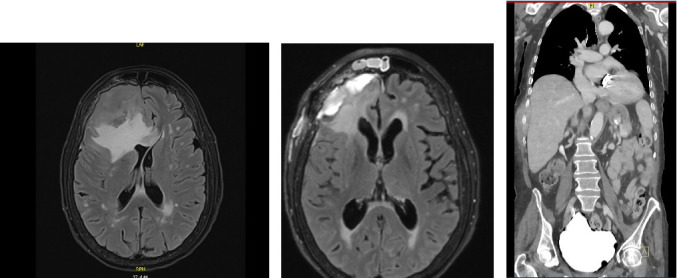

Early T-cell precursor acute lymphoblastic leukemia/lymphoma (ETP-ALL/LBL) is a high-risk and biologically distinct subset of T-cell acute lymphoblastic leukemia, typically characterized by leukemic involvement of bone marrow, peripheral blood, and mediastinal structures. Central nervous system (CNS) involvement is typically a secondary manifestation [1, 2, 3]. We report a rare case of isolated CNS presentation of ETP-ALL/LBL in a 73-year-old woman who presented with progressive neurological symptoms. Imaging revealed a large right frontal extra-axial mass. Systemic evaluation, including peripheral blood flow cytometry and CT imaging of chest, abdomen, and pelvis, showed no evidence ofsystemic disease. Surgical resection and subsequent histopathology confirmed the diagnosis of ETP-ALL/LBL. A bone marrow biopsy was deffered to the patient's preference and rapid clinical deterioration. This case underscores the diagnostic and therapeutic challenges of CNS-restricted leukemic presentations and highlights the need for early recognition and CNS-directed diagnostic evaluation.